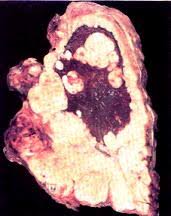

Lung Cancer Symptoms Australia / Lung Cancer Awareness Month Connect Ability Australia - People with lung cancer often experience signs and symptoms of the cancer, as well as side effects of treatment.. Stage 4a lung cancer, in which cancer has spread within the chest to the opposite lung; Persistent cough or a new or changed wheeze (or both) It is the fifth most common cancer in australia, accounting for 9% of all cancers diagnosed. People with lung cancer often experience signs and symptoms of the cancer, as well as side effects of treatment. It is generally recognised that early diagnosis of lung cancer could be an important factor in improving both the survival rate and patients' quality of life.

Some of the most common are horner's syndrome, superior vena cava syndrome, and paraneoplastic syndrome. Lung cancer signs and symptoms can be difficult to detect, and is often discovered when it is more advanced. A person diagnosed with lung cancer may also have symptoms such as fatigue, weight loss, hoarse voice, wheezing, difficulty swallowing, abdominal or joint pain, and enlarged fingertips (finger clubbing). Sores or ulcers that don't heal. A number of studies have identified certain symptoms to be more prevalent at various stages of the disease development.

November Lung Cancer Awareness Month Edmonton Family Medical Centre from edmontonfmc.com.au A number of studies have identified certain symptoms to be more prevalent at various stages of the disease development. Cancer australia was established by the australian government in 2006 to benefit all australians affected by cancer, and their families and carers. Changes to the voice such as hoarseness. Chronic, hacking, raspy coughing, sometimes with mucus that has blood in it; Symptoms of lung cancer at stage 4. It is generally recognised that early diagnosis of lung cancer could be an important factor in improving both the survival rate and patients' quality of life. Lung cancer has the lowest survival rate of all cancers in adults, with only 13% of affected individuals in australia surviving for five or more years following a diagnosis. Most factors include the patient's outlook, treatment plan and overall health.

Lung cancer stage 4 can not be treated, so the question arises only about how much a person left to live. It is the fifth most common cancer in australia, accounting for 9% of all cancers diagnosed. It was estimated that there would be 3,258 new cases of lung cancer diagnosed in australian in 2020. Pancoast tumors rarely produce symptoms related to the lungs themselves, such as chest pain or cough. View more get the latest lung foundation australia news.

Stay up to date with the latest information, news, services and events by signing up to our database. While community awareness of the link between smoking and lung cancer in australia is high 18 , awareness of lung cancer symptom recognition is unknown. Each year, about 12,200 australians are diagnosed with lung cancer. If you have a moist cough, your mucus should be clear or white in colour. There can be many different reasons for having a persistent cough; Pancoast tumors rarely produce symptoms related to the lungs themselves, such as chest pain or cough. Lung cancer is the fifth most common cancer in australia and accounts for 9% of all cancers. A number of studies have identified certain symptoms to be more prevalent at various stages of the disease development. Lung cancer signs and symptoms can be difficult to detect, and is often discovered when it is more advanced. A person diagnosed with lung cancer may also have symptoms such as fatigue, weight loss, hoarse voice, wheezing, difficulty swallowing, abdominal or joint pain, and enlarged fingertips (finger clubbing). Lung cancer is the fifth most common cancer australia with over 11,000 people diagnosed in 2012. Stage 4c lung cancer, in which cancer has spread to one or multiple. If it spreads you might develop other symptoms like nausea, headaches and pain in other parts of your body.